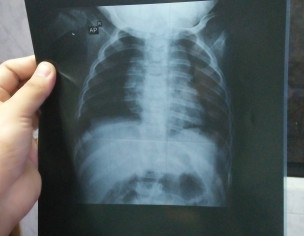

My dauggtr is 8 is having fever on and off frm.1 occurs every 6 or 8 100' dr prescibed tst which i m has done 5 day courses of zetro and fevsr is there.m postng repors amd chest xray. Kindly guide